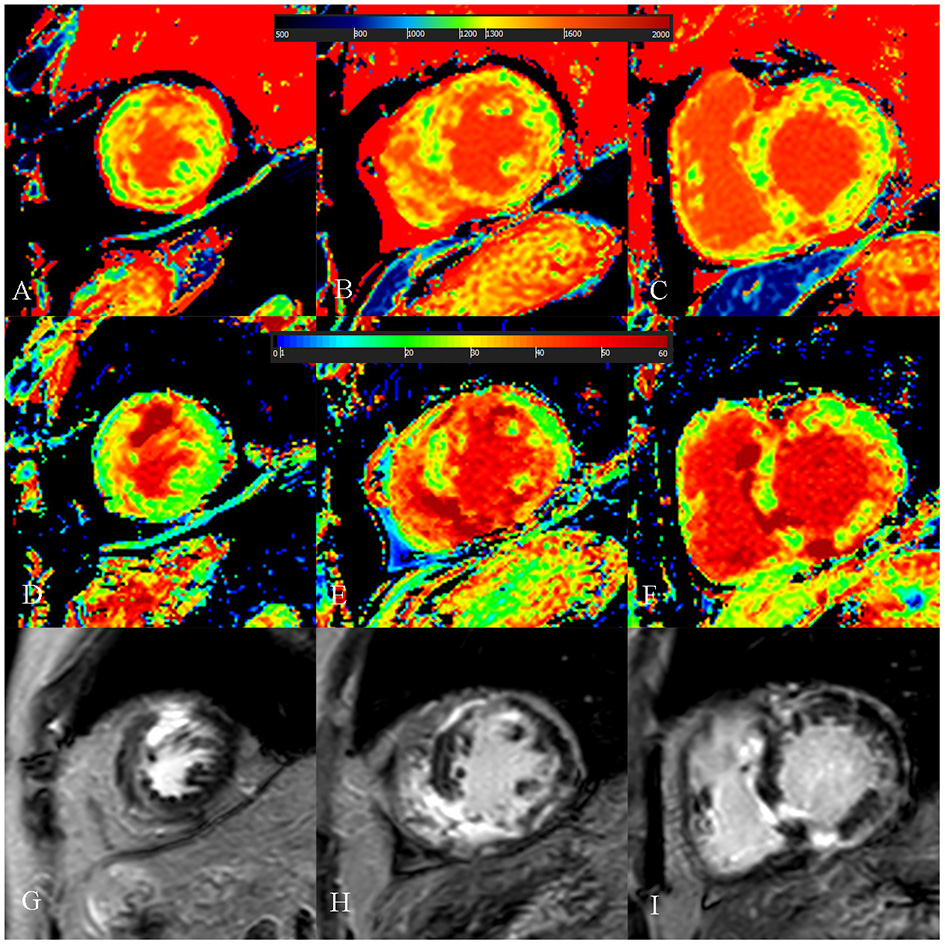

Figure 6

A 52-year-old male with burned out phase hypertrophic cardiomyopathy. (A–C) Native T1 mapping of the apical, mid-, and basal portions of the left ventricular (LV) myocardium revealed higher global native T1 (1,380.7 ms). (D–F) Extracellular volume fraction (ECV) of the apical, mid-, and basal portions of the LV myocardium showed higher global ECV (32.8%). (G–I) Late gadolinium enhancement (LGE) images of the apical, mid-, and basal portions of the LV myocardium showed multiple LGE. The maximal LV wall thickness was 13 mm, left atrial diameter was 53 mm, and the LV outflow tract gradient pressure was 2 mmHg. He had non-sustained ventricular tachycardia, but no family history of sudden cardiac death (SCD), and unexplained syncope. He had LGE/LV mass ≥15% (elevated LGE/LV mass: 56.2%) and end-stage systolic dysfunction but no apical aneurysm. He was stratified with low SCD risk under the 2014 European Society of Cardiology guidelines (5-year SCD probability: 3.39%) and high SCD risk under the enhanced American College of Cardiology/American Heart Association guidelines. He underwent cardiac transplantation 35 months after cardiac MRI examination. End-stage systolic dysfunction strongly indicated poor outcome in this patient. However, increased global native T1 mapping and ECV values could also suggest that the patient was likely to be at high risk of SCD and needs further treatment.